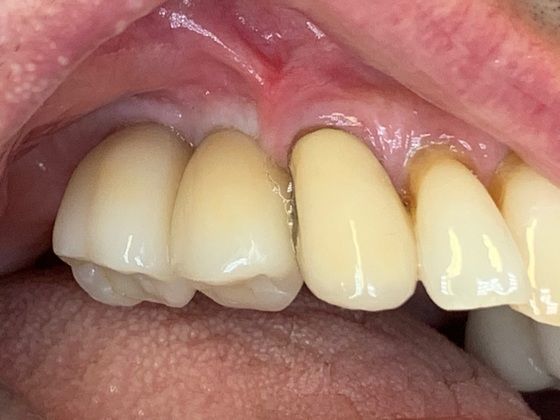

Patients moving to Austin often need a restorative dentist to complete their case started prior to them moving here. This was a pair of BioHorizon dental implants in the patient's upper right quadrant. The patient moved from Chicago to Austin this year and needed help restoring his newly placed implants. We were easily able to fabricate two custom dental crowns that were delivered effortlessly and painlessly in a short appointment.